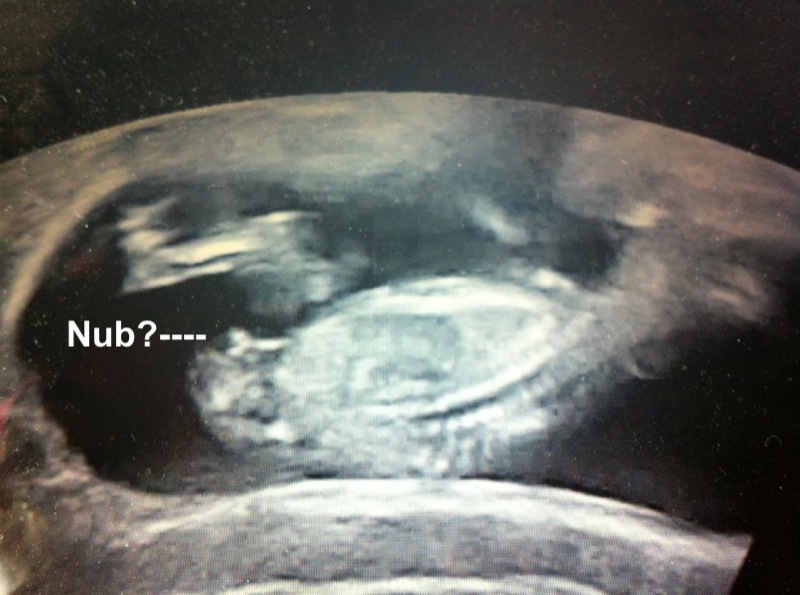

Here is my scan at 12w 4d but baby measured at 13w 1d baby would not sit still so couldnt get a clear shot i went through ultrasound and this is what i found would love to hear what you think thanks guys